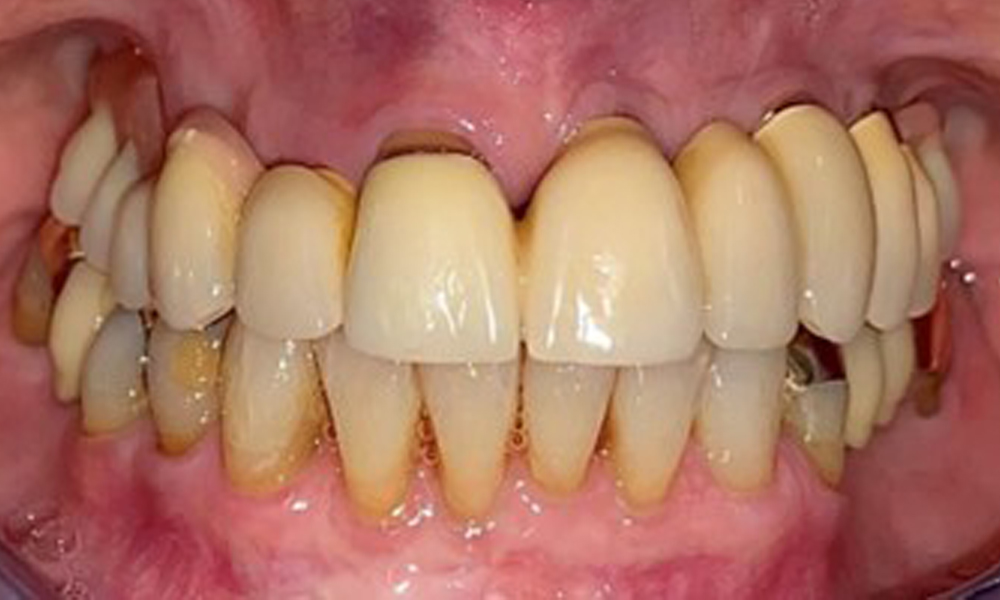

The patient was fitted with a combined removable maxillary telescopic prosthesis more than 25 years ago (Fig. 1, Fig. 2, Fig. 3) and is very happy with her dentures. The patient has an adequate fixed denture for the mandible (Fig. 4).

The dental findings are as follows: Combined removable implant and tooth-supported telescopic prostheses on implants 15, 13, 21, 23, 24, 25 and tooth 11 (Fig. 1, Fig. 2, Fig. 3). The patient was fitted with a fixed mandibular denture. Adequate bridges were present over 37 to 34 and 45 to 47 (Fig. 4), the crown margins were intact and there were no active caries. A composite filling with a marginal gap was present on tooth 43. There was mandibular gingival recession, exposing 1 to 3 mm of root surface. This also applies to 11.

Occlusal view of the mandible.

Fig. 4: Occlusal view of the mandible.